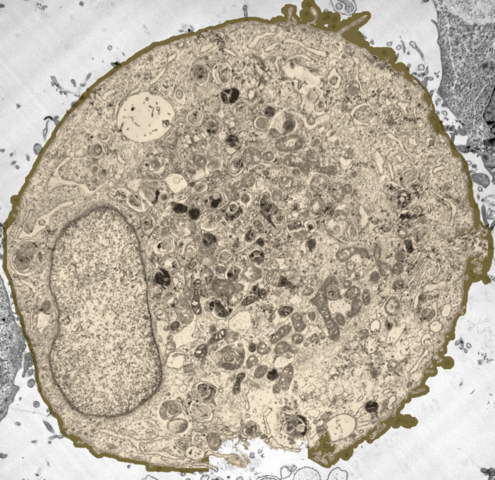

Realiza descubrimientos en microbiología, en su puesto como comerciante de telas, a través de un microscopio. Descubre protozoarios, espermatozoides. Estudió glóbulos rojos y la anatomía de diversos mamíferos e insectos.